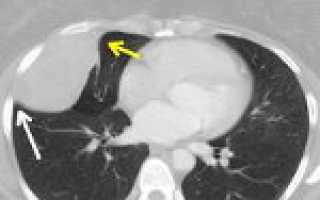

Доброкачественные опухоли плевры обычно выявляются при рентгенологическом исследовании (полипозиционной рентгенографии грудной клетки, рентгеноскопии легких). На рентгенограммах определяется полукруглая или полуовальная гомогенная тень с четкими очертаниями, прилежащая своим широким основанием к тени ребер, реже — диафрагмы либо средостения. При рентгеноскопии легких хорошо видно, как опухоль, исходящая из париетальной плевры, при дыхании смещается вместе с ребрами. Структура ребер, как правило, не изменена прилежащими к ним доброкачественными опухолями плевры.

Уточняющая роль в диагностике опухолей плевры отводится КТ и МРТ легких, УЗИ плевральной полости. Под контролем КТ или УЗИ проводится пункционная биопсия плевры с последующим исследованием биоптата; при наличии экссудата выполняется плевральная пункция. При недоступности опухоли плевры для трансторакальной биопсии прибегают к диагностической торакоскопии (плевроскопии).